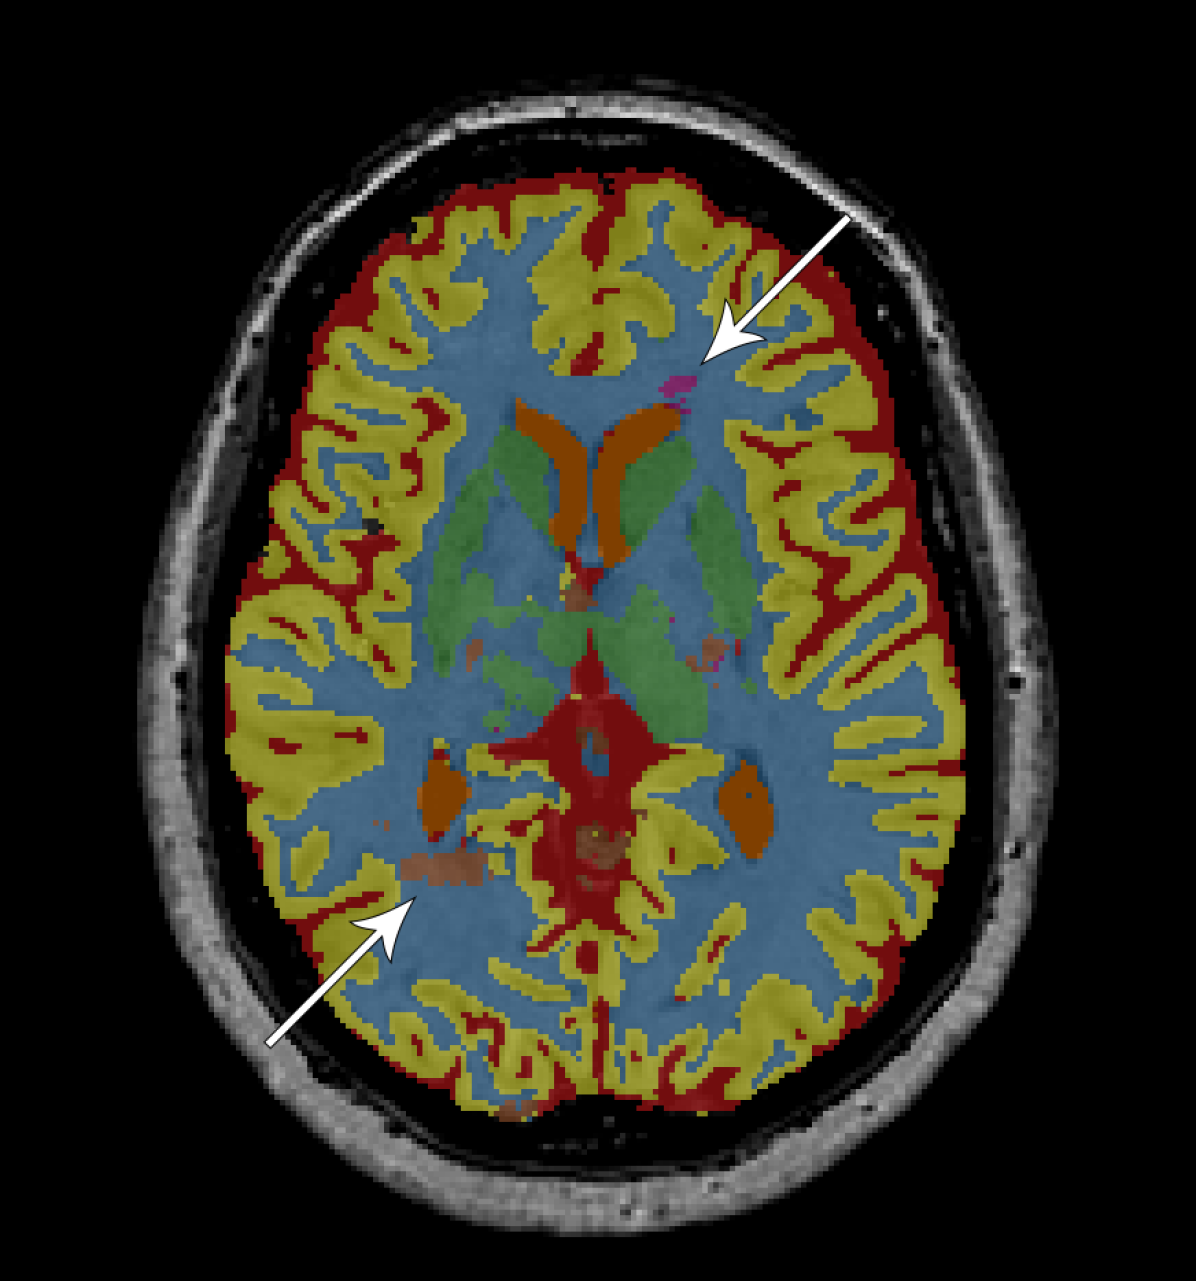

Figure 2 provides a visual comparison between the segmentations obtained with and without adversarial training, showing that the adversarial approach generally resulted in less noisy segmentations. The same can be seen from the total number of 3D components (including the background class) that compose the segmentations. For the adult subjects, the number of components per image () decreased from to using the fully convolutional network and from to using the dilated network. For the elderly subjects, the number of components per image () decreased from to using the fully convolutional network and from to using the dilated network.

We have presented an approach to improve brain MRI segmentation by adversarial training. The results showed improved segmentation performance both qualitatively (Figure 2) and quantitatively in terms of DC (Figure 3). The improvements were especially clear for the deeper, more difficult to train, fully convolutional networks as compared with the more shallow dilated networks. Furthermore, the approach improved structural consistency, e.g. visible from the reduced number of components in the segmentations. Because these improvements were usually small in size, their effect on the DC was limited.